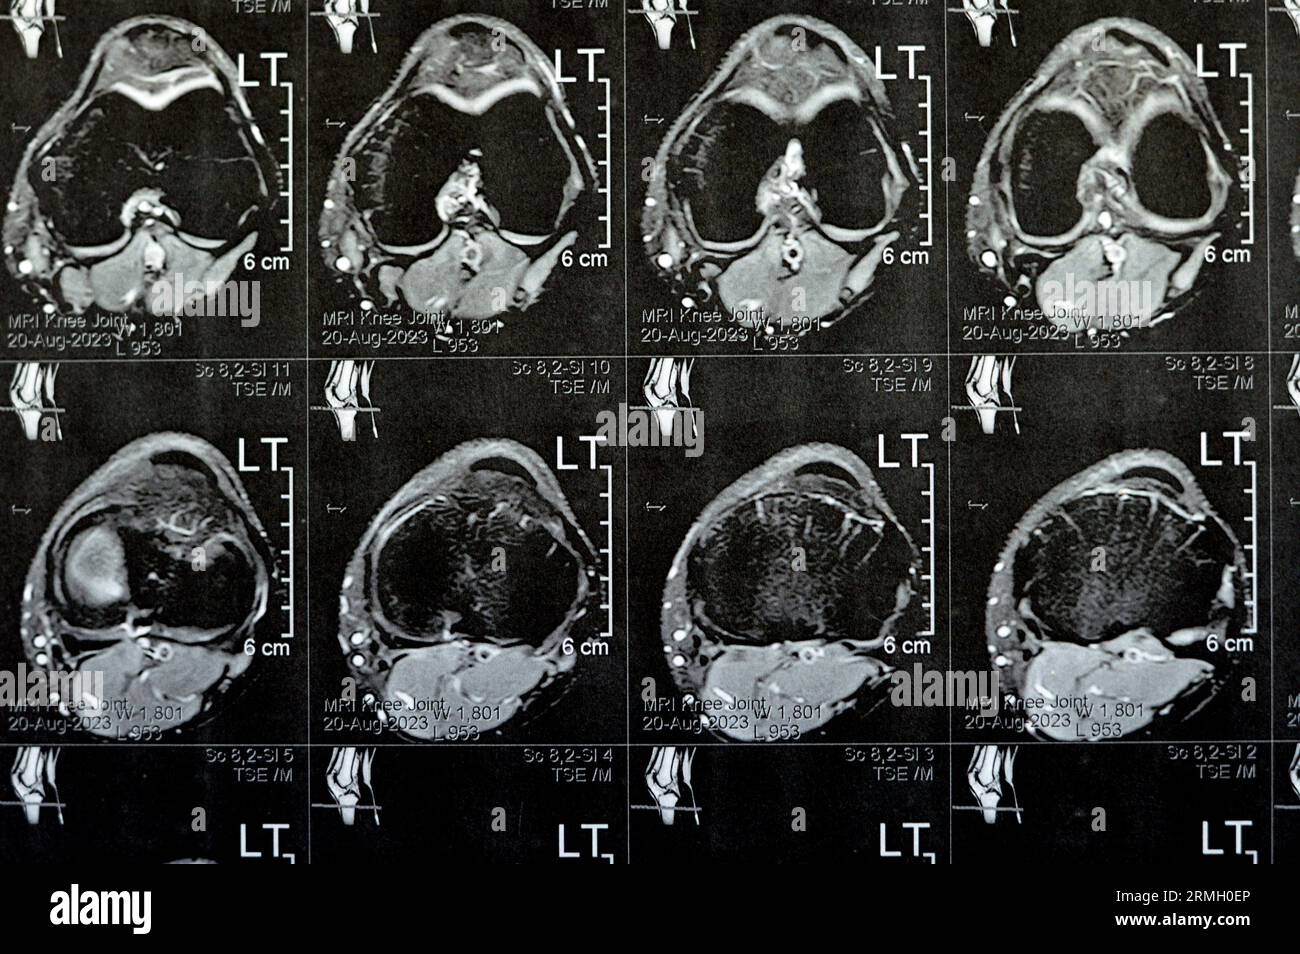

MRI of left knee joint showing minimal joint effusion, PHMM Posterior Anterior Horn Disease Mri Incomplete spinal cord syndromes are reviewed, with descriptions of the relevant spinal cord anatomy and common causes of these syndromes and with emphasis on the correlation of anatomic and imaging findings with clinical manifestations. Emg/ncs, serum and urine electrophoresis,. Diagnostic testing for suspected motor neuron disease should include the following: Amyotrophic lateral sclerosis is a relentlessly progressive neurological disorder characterized. Anterior Horn Disease Mri.

MRI of Left Knee Joint Showing Minimal Joint Effusion, PHMM Posterior Anterior Horn Disease Mri Incomplete spinal cord syndromes are reviewed, with descriptions of the relevant spinal cord anatomy and common causes of these syndromes and with emphasis on the correlation of anatomic and imaging findings with clinical manifestations. The electromyography, nerve conduction studies, mri of the. Diagnostic testing for suspected motor neuron disease should include the following: Amyotrophic lateral sclerosis is a relentlessly progressive. Anterior Horn Disease Mri.

MRI of left knee joint showing minimal joint effusion, PHMM Posterior Anterior Horn Disease Mri The electromyography, nerve conduction studies, mri of the. Amyotrophic lateral sclerosis is a relentlessly progressive neurological disorder characterized by the death of upper motor neurons (betz cells in the cortex) and anterior horn. Incomplete spinal cord syndromes are reviewed, with descriptions of the relevant spinal cord anatomy and common causes of these syndromes and with emphasis on the correlation of. Anterior Horn Disease Mri.

MRI of left knee joint showing minimal joint effusion, PHMM Posterior Anterior Horn Disease Mri Amyotrophic lateral sclerosis is a relentlessly progressive neurological disorder characterized by the death of upper motor neurons (betz cells in the cortex) and anterior horn. Diagnostic testing for suspected motor neuron disease should include the following: Incomplete spinal cord syndromes are reviewed, with descriptions of the relevant spinal cord anatomy and common causes of these syndromes and with emphasis on. Anterior Horn Disease Mri.

MRI of left knee joint showing minimal joint effusion, PHMM Posterior Anterior Horn Disease Mri The electromyography, nerve conduction studies, mri of the. Flexion cervical mr imaging is a very useful investigation in diagnosing hirayama disease. Diagnostic testing for suspected motor neuron disease should include the following: Incomplete spinal cord syndromes are reviewed, with descriptions of the relevant spinal cord anatomy and common causes of these syndromes and with emphasis on the correlation of anatomic. Anterior Horn Disease Mri.

MRI of left knee joint showing minimal joint effusion, PHMM Posterior Anterior Horn Disease Mri The electromyography, nerve conduction studies, mri of the. Incomplete spinal cord syndromes are reviewed, with descriptions of the relevant spinal cord anatomy and common causes of these syndromes and with emphasis on the correlation of anatomic and imaging findings with clinical manifestations. Emg/ncs, serum and urine electrophoresis,. Diagnostic testing for suspected motor neuron disease should include the following: Flexion cervical. Anterior Horn Disease Mri.

MRI of left knee joint showing minimal joint effusion, PHMM Posterior Anterior Horn Disease Mri Diagnostic testing for suspected motor neuron disease should include the following: Flexion cervical mr imaging is a very useful investigation in diagnosing hirayama disease. The electromyography, nerve conduction studies, mri of the. Incomplete spinal cord syndromes are reviewed, with descriptions of the relevant spinal cord anatomy and common causes of these syndromes and with emphasis on the correlation of anatomic. Anterior Horn Disease Mri.

MRI of left knee joint showing minimal joint effusion, PHMM Posterior Anterior Horn Disease Mri Incomplete spinal cord syndromes are reviewed, with descriptions of the relevant spinal cord anatomy and common causes of these syndromes and with emphasis on the correlation of anatomic and imaging findings with clinical manifestations. The electromyography, nerve conduction studies, mri of the. Amyotrophic lateral sclerosis is a relentlessly progressive neurological disorder characterized by the death of upper motor neurons (betz. Anterior Horn Disease Mri.